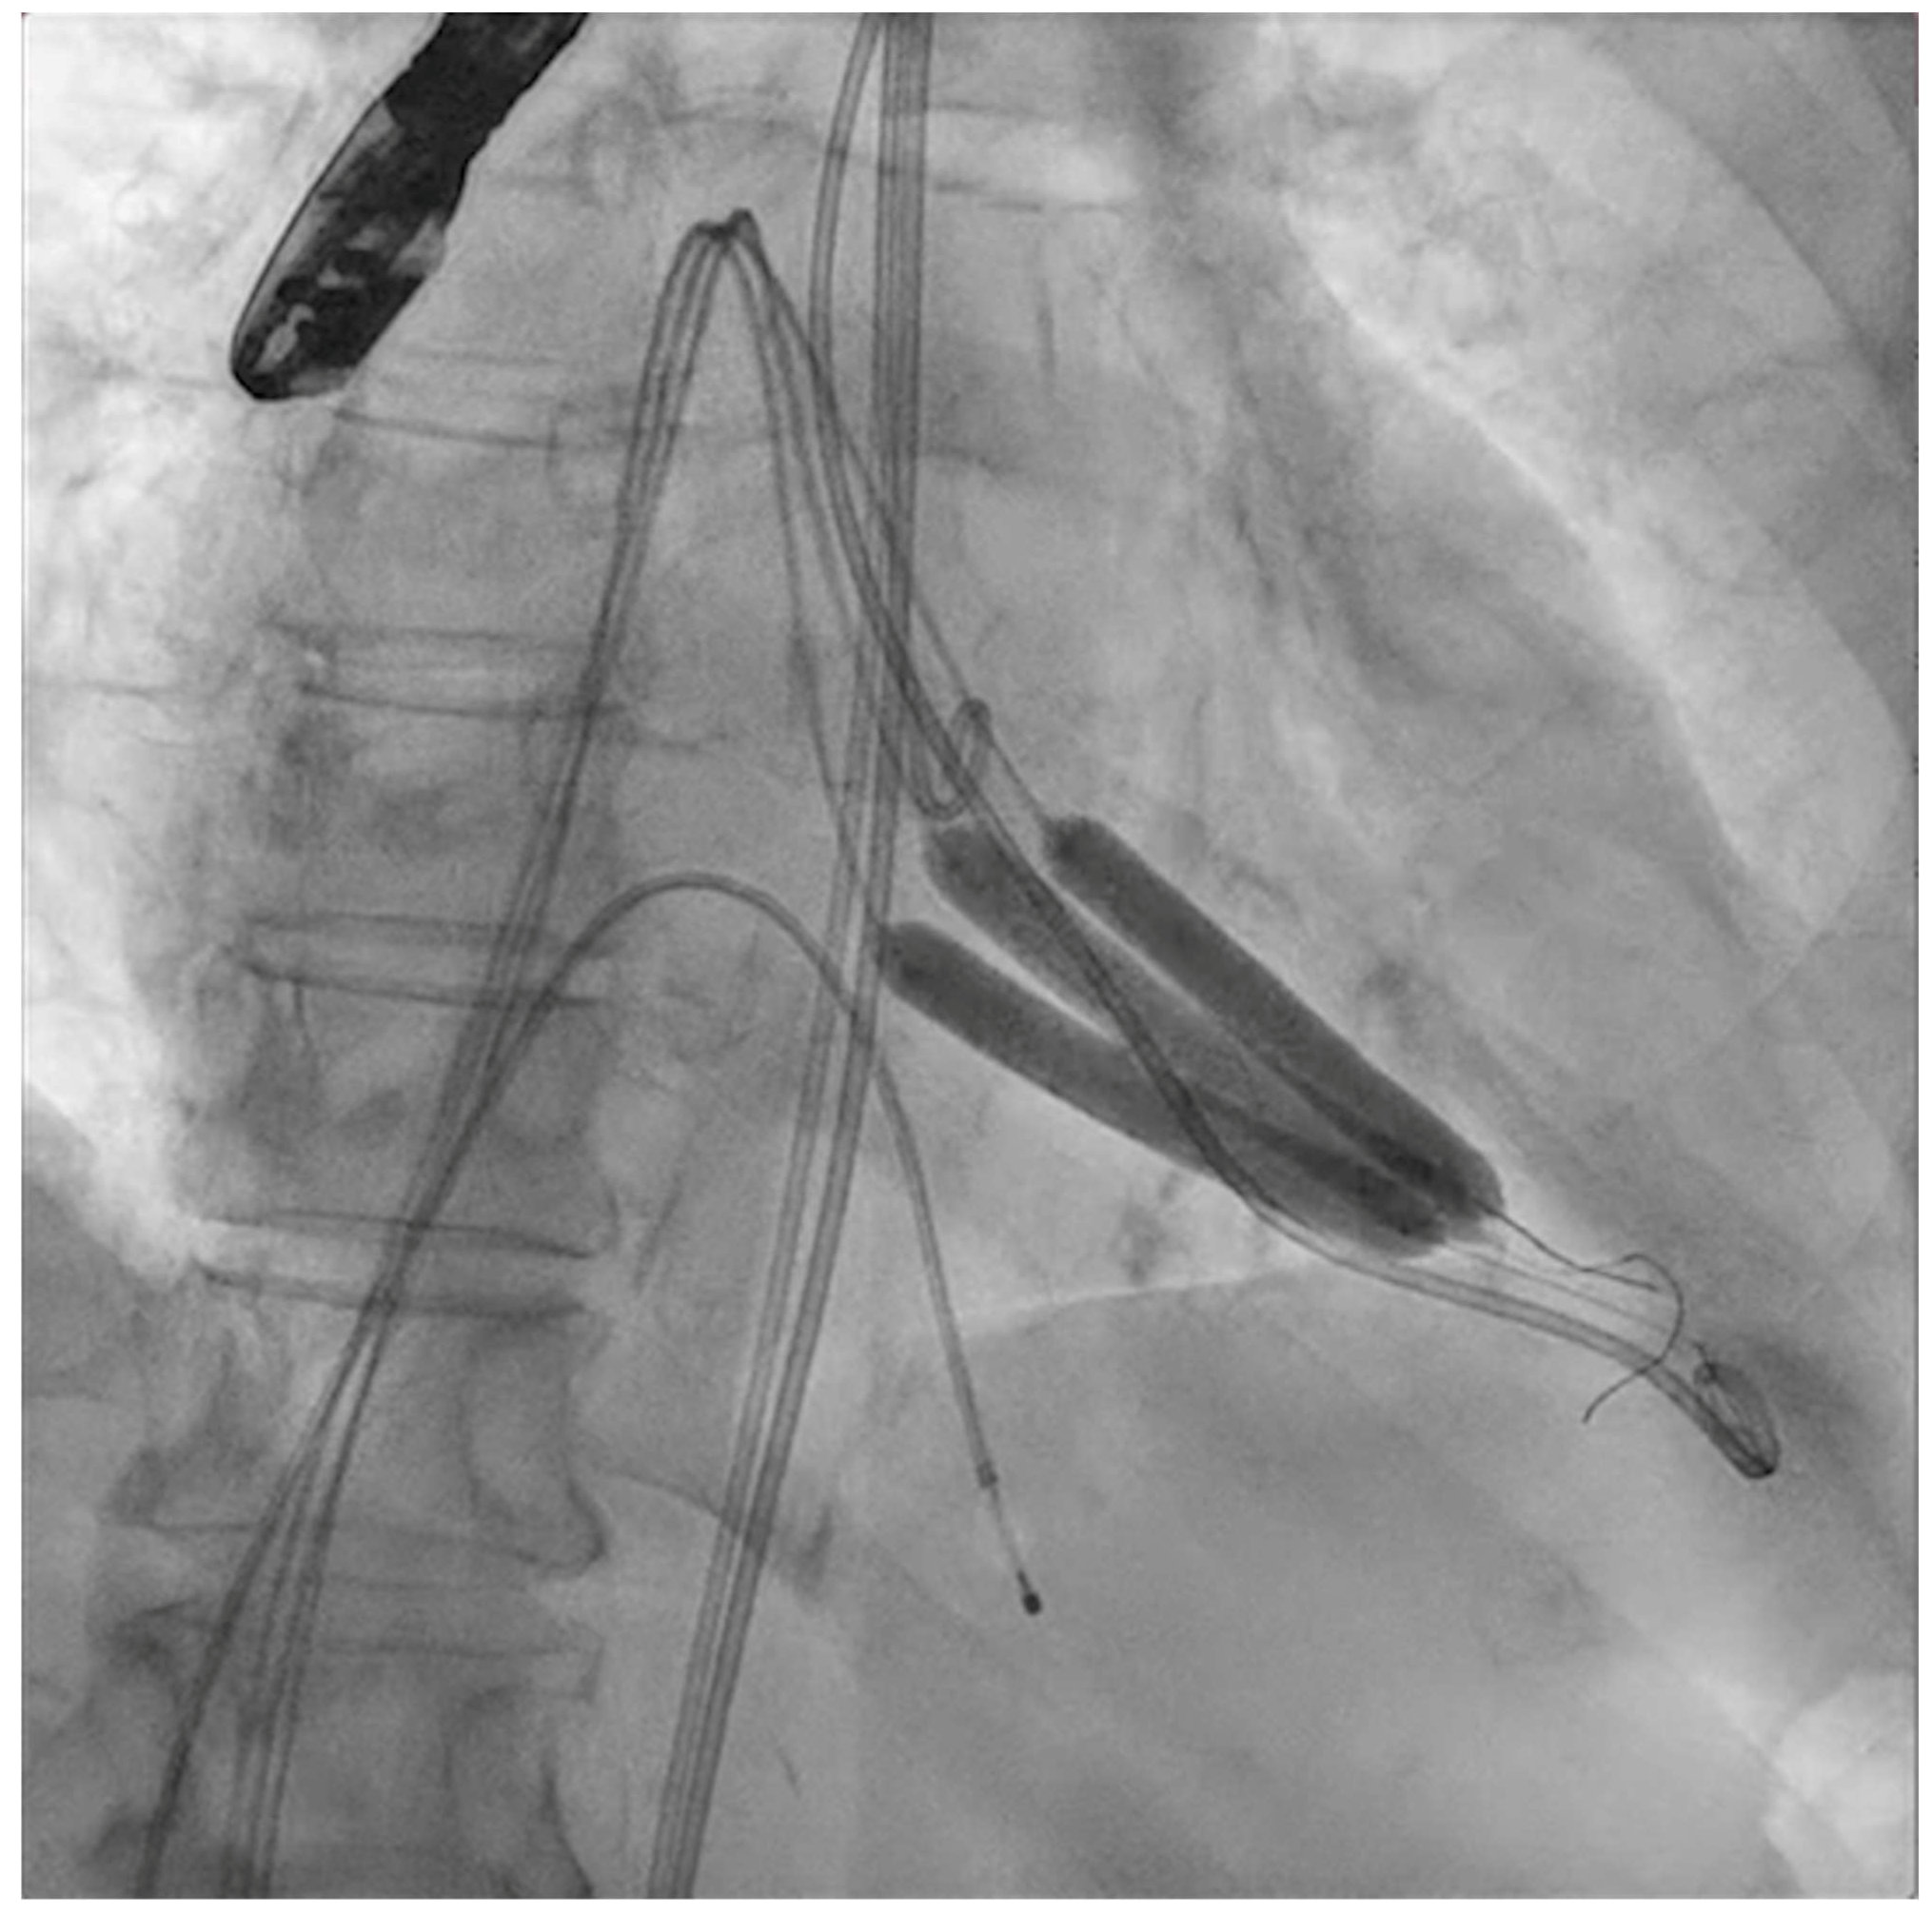

The next steps consist of crossing the mitral valve with three long high-support 0.014´´ wires downstream into the left ventricle (LV) (Figure 2) and then advancing three lithotripsy balloons (Shockwave Medical) across the mitral valve; with rapid pacing (120 beats/min), simultaneous inflations of all balloons will deliver a total of 90 pulses from each balloon (Figure 3). Finally, access to the LV has to be attained again with the Safari wire to complete PMC with large balloons appropriately sized to the mitral valve area and diameters (Figure 4). Embolic protection devices are encouraged to avoid neurological or systemic ischemic events due to calcific debris.

Figure 2.

Three angioplasty wires crossing the mitral valve into the left ventricle.

Simultaneous inflation of three 7 × 60 mm shockwave balloons on the mitral valve for lithotripsy applications.

Figure 4.

Percutaneous mitral commissurotomy (non-compliant 26 mm balloon).